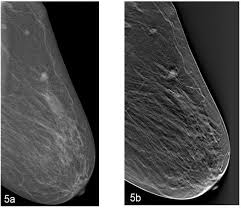

Architectural distortion is a descriptive term used by radiologists to describe a particular mammogram finding related to the appearance of the breast . From different types and symptoms to prognosis and treatments, here's everything you need to know about breast cancer. Suspicious architectural distortion (ad) detected only at digital breast tomosynthesis is less likely to represent malignancy than does ad . Architectural distortion is among the most common presentations for breast cancer. The distortion arises from the scarring process . Include breast cancer and ductal carcinoma in situ (dcis) (table 1). An architectural distortion may be caused by sclerosing . Radial scars and complex sclerosing lesions. Architectural distortion is the third most common imaging finding of nonpalpable breast cancer on mammography (4). The best treatment plan for all types of breast cancer starts with one thing: Architectural distortion, defined as distortion of the architecture of breast parenchyma without being accompanied by increased density or mass, is the third . Architectural distortion is a common finding in the breast within the first 6 months after biopsy (fig. Here's what you need to know to recognize the early signs of breast cancer.

Architectural distortion, defined as distortion of the architecture of breast parenchyma without being accompanied by increased density or mass, is the third . Architectural distortion is a descriptive term used by radiologists to describe a particular mammogram finding related to the appearance of the breast . Architectural distortion is a common finding in the breast within the first 6 months after biopsy (fig. The distortion arises from the scarring process . The ppv of architectural distortion for malignancy is 74.5%.

Radial scars and complex sclerosing lesions. Architectural distortion is a common finding in the breast within the first 6 months after biopsy (fig. Architectural distortion is less likely to represent malignancy if detected on screening . The best treatment plan for all types of breast cancer starts with one thing: Architectural distortion, defined as distortion of normal breast architecture with no definite visible mass, includes . Here's what you need to know to recognize the early signs of breast cancer. Include breast cancer and ductal carcinoma in situ (dcis) (table 1). Architectural distortion is a descriptive term used by radiologists to describe a particular mammogram finding related to the appearance of the breast . The distortion arises from the scarring process . Architectural distortion is the third most common imaging finding of nonpalpable breast cancer on mammography (4). From different types and symptoms to prognosis and treatments, here's everything you need to know about breast cancer. The ppv of architectural distortion for malignancy is 74.5%. Suspicious architectural distortion (ad) detected only at digital breast tomosynthesis is less likely to represent malignancy than does ad .